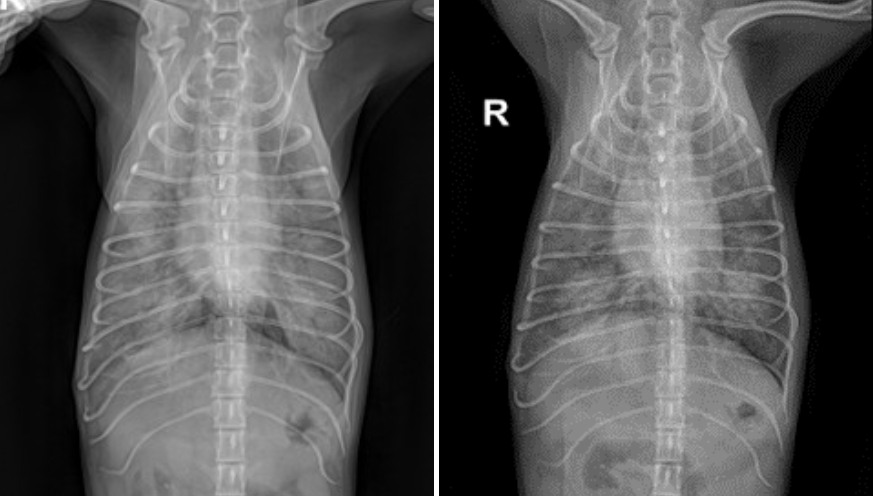

치료 2일차(좌) /치료 3일차(우)

입원 2일차, 테오는 호흡 상태가 점차 악화되었으며 방사선 검사상에서도 폐 상태가 이전보다 악화된 소견이 확인되었습니다.

새벽 시간대에 전반적인 상태가 급격히 나빠지며 응급 상황 가능성이 있어 보호자님 면회를 추가적으로 진행하였습니다.